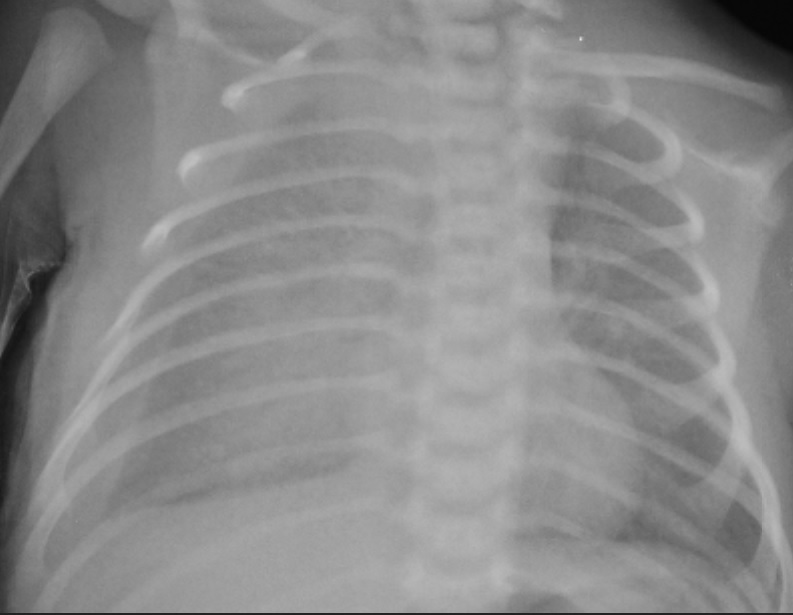

A 2900g female term newborn born by cesarean section to a 21-year-old primigravida mother. Bilateral pleural effusion and polyhydramnios were detected on follow-up at the 36th week of gestation. After delivery, the newborn was intubated immediately due to respiratory depression. Bilateral thoracentesis was carried out in the delivery room. The chest x-ray showed bilateral pleural effusion (Fig.1). Since the pleural effusion re-accumulated rapidly, the chest tube (right side) was placed on postnatal day 1. The pleural fluid was colorless and its analysis revealed pH 7.3, density 1005, lactate dehydrogenase 164 IU/L, protein 1.1g/dl, cholesterol 27 mg/dl, triglyceride 13 mg/dl, white cell count with 5% lymphocytes and 90% polymorphs. Chromosomal analysis, echocardiogram, cranial, and abdominal ultrasound (USG) examinations of the baby were normal. No viral or bacterial infection was detected on laboratory workup.

Chest x-ray demonstrating the presence of pleural effusion at 30 min of age.